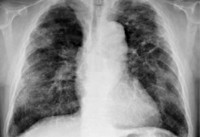

При выставлении диагноза и определении вида силикатоза учитывается стаж работы в условиях повышенного пылеобразования и условия труда. При аускультации выслушивается жесткое или ослабленное дыхание, сухие хрипы, иногда, на отдельных участках - влажные хрипы. При рентгенологическом обследовании в большинстве случаев выявляется сетчато-тяжистый фиброз, утолщение междолевой плевры. Определенную информацию о степени выраженности дыхательной недостаточности может дать спирометрия, анализ газового состава крови. При отдельных формах силикатоза в мокроте могут выявляться «асбестовые тельца», «слюдяные тельца», «талькозные тельца», что позволяет подтвердить этиологический диагноз.